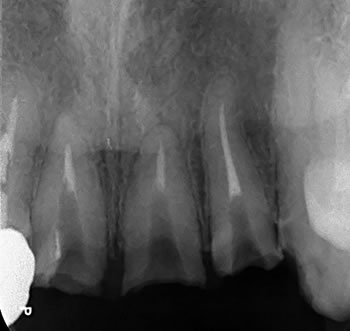

県外からお引っ越しされて来た患者様ですが、前医からの紹介状にて事故で折れた歯牙のエキストル―ジョン(廷出)と根管治療のご依頼でした。

折れた歯を矯正的に引き出すのですが、その後は当然「差し歯」を入れますので、根管治療(根の治療)もしっかりしなくちゃ! |

折れた歯牙が歯肉縁下におよぶので、保存するには厳しい状況、、、3本ありますので、まずは真ん中1本の根管治療をして |